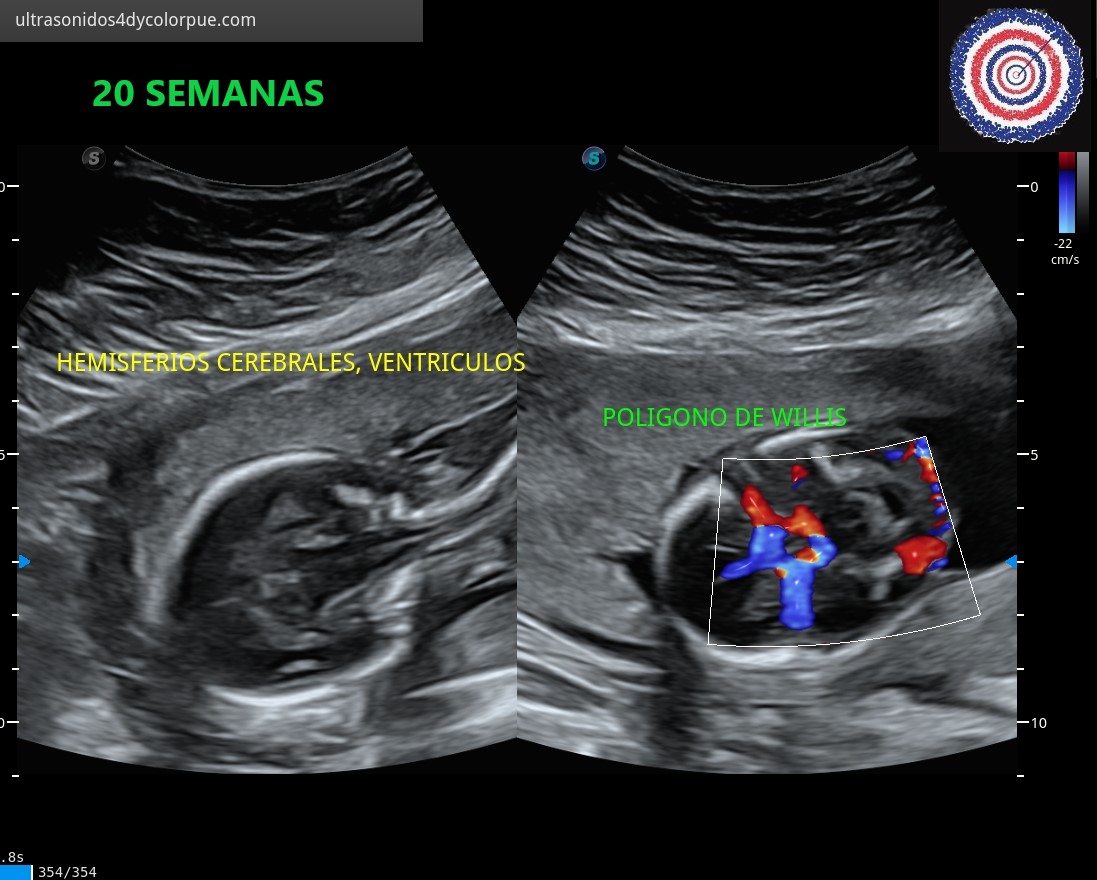

En Ginecología y Obstetricia el ultrasonido DOPPLER-COLOR Y DE ALTA RESOLUCIÓN es muy importante para realizar estudios precisos; se puede checar cuando hay embarazo desde las 5 semanas y media a partir del inicio de la fecha de la última regla; con el ULTRASONIDO TRANSVAGINAL se pueden valorar con mayor precisión, los embarazos desde las primeras semanas y se puede revisar que no haya malformaciones ni complicaciones que alteren el curso del embarazo. Se han establecido parámetros muy claros para la evaluación correcta de cada embarazo y en la mayoría de los casos se puede confirmar anormalidades o alteraciones o descartarse.

El ULTRASONIDO ESTRUCTURAL nos permite valorar la apariencia de los órganos y sistemas del cuerpo del bebé, se observa el funcionamiento del corazón y grandes vasos, la presencia de orina en la vejiga, la morfología y densidad interna de los pulmones, riñones, hígado y la anatomía y vascularización del cerebro y de todo el cuerpo, lo que nos da confianza en un pronóstico óptimo.